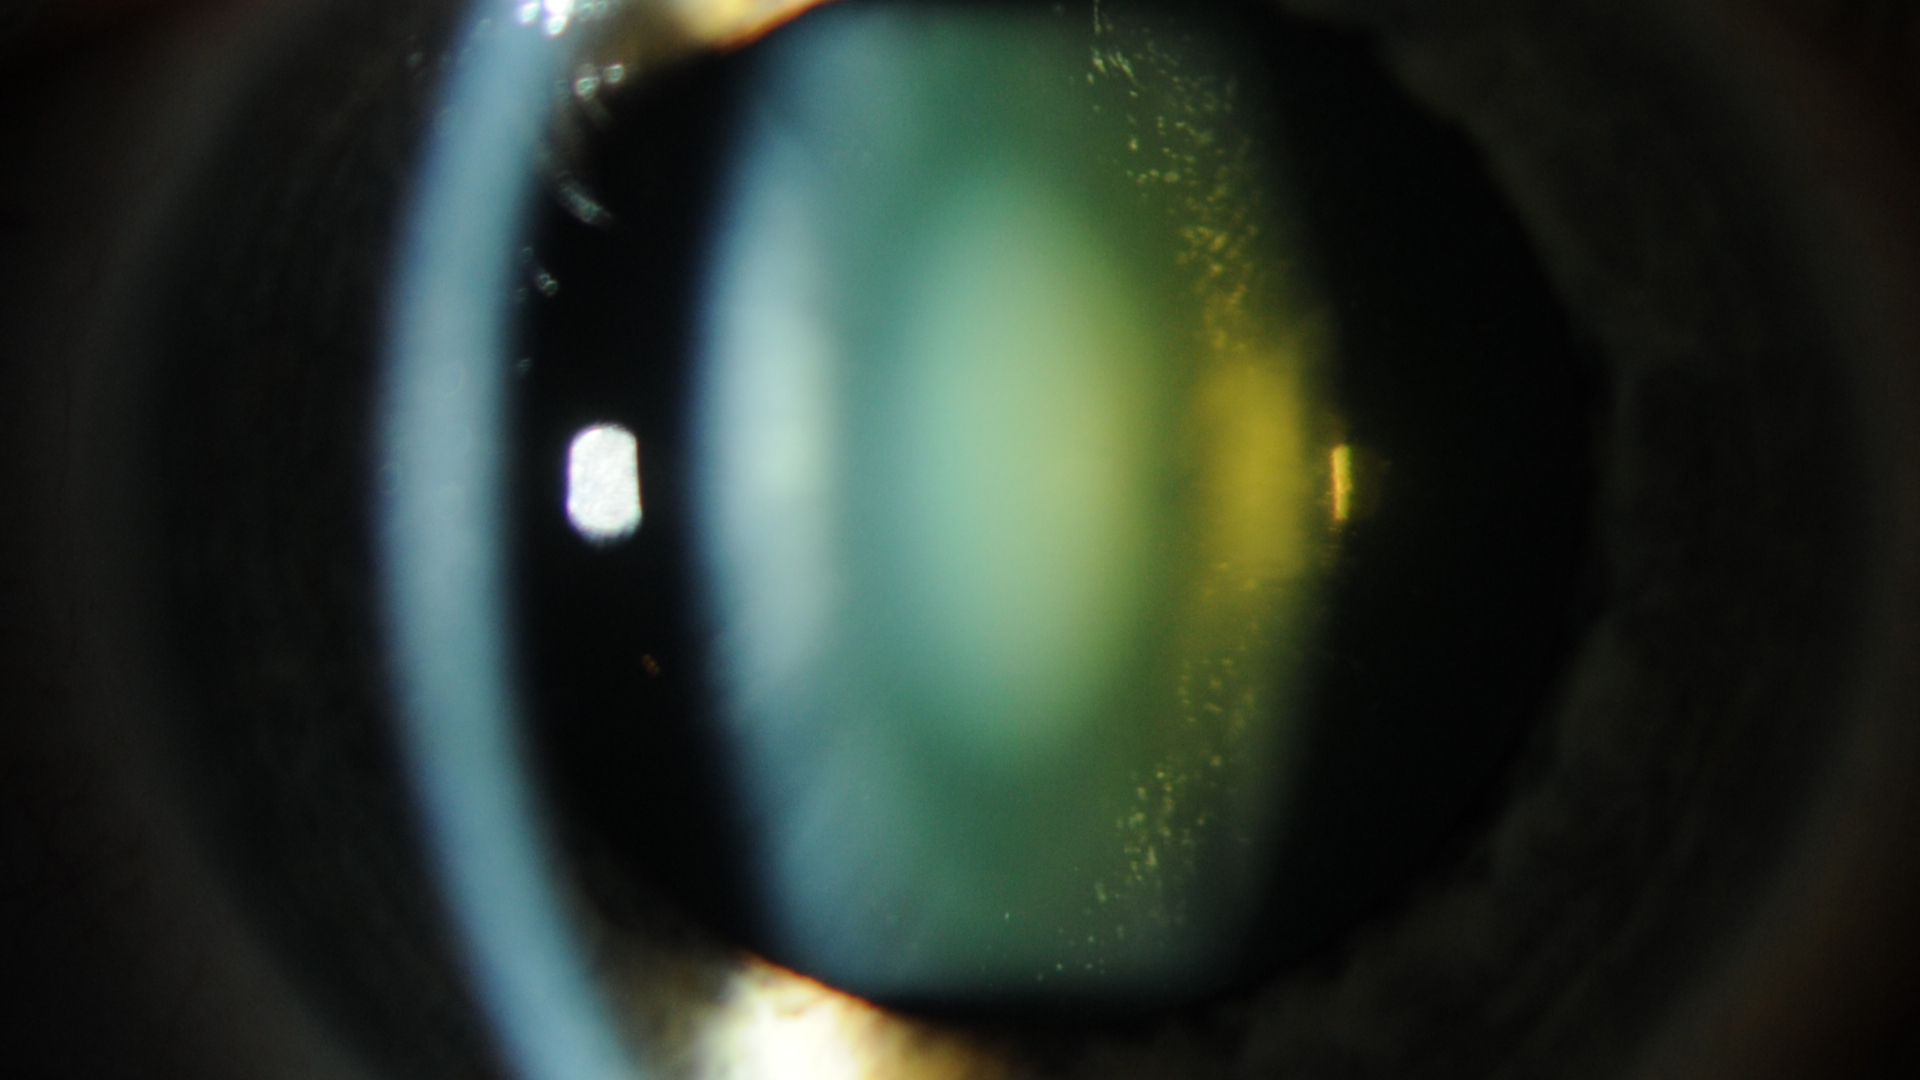

Katarakt, bulanık görmenin en yaygın nedenlerinden biridir. Bunun için standart tedavi, kataraktlı lensin cerrahi olarak çıkarılması ve göz içi lensin yerleştirilmesidir. Katarakt ameliyatını takiben hastanın rahat bir şekilde iyileşmesi için çeşitli ameliyat sonrası yönergeler vardır. Günümüz teknolojisinin geldiği seviye itibarıile, katarakt cerrahisi geçmişe göre daha basit hale geldi.